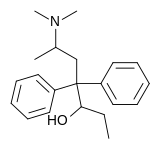

Methadols

Structures

| Other open chain opioids | ||||

|---|---|---|---|---|

|

|

|

Noracetylmethadol | |